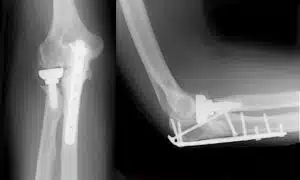

المعلومات الشاملة لعملية تركيب شريحة ومسامير في الكوع

المفاصل الصناعية هي بديل للمفاصل الطبيعية التالفة، وتُصنع من مواد عالية الجودة كالبلاستيك والمعدن.

يعد دكتور عمرو أمل (استشاري جراحة العظام والمفاصل واصابات الملاعب) من أفضل الأطباء في تركيب المفاصل الصناعية في مصر، مثل عمليات تغيير مفصل الحوض وتغيير مفصل الكوع، لخبرته الواسعة واستخدامه لأحدث المعدات.